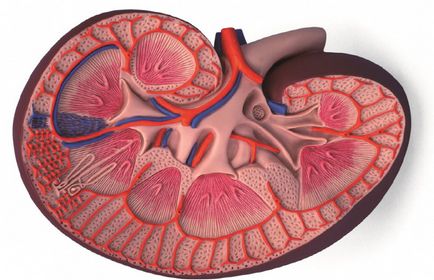

vese parenchyma sejtek egy csoportja, amelyek állnak a kortikális és agyi anyag és megtartják azt a képességüket, hogy regenerálódni. Annak érdekében, hogy megfelelően állapotának megállapítása ilyen kapszula, akkor kell használni ultrahang.

Miután érzékelte, renális diffúziós kell végeznie teljes vizsgálatának a test fejlesztés különböző patológiás állapotok és másodlagos betegségek. Ezek a betegségek módosítások kíséretében vese méretének. Jelenlétében semmilyen akut vese betegségek növekvő átmérőjű, ami megnehezíti a közeli szervekben. Során súlyosbodása krónikus betegség megfigyelt elvékonyodása parenchyma, ami tovább jár csökkent a renális héj vastagsága.

Felmérések segítségével ultrahang az orvos határozza meg egységes szerkezetben a vese membránok, átméretezés, a jelenléte a gyulladásos folyamatok. Ha szükséges, akkor lehet rendelni egy további vizsgálat, így teljes képet a betegség. Csak akkor tudjuk beszélni a végső diagnózis és a fejlesztési kezelési rendszerek.

Elvékonyodása veseparenchyma

A betegség jelenlétében krónikus problémák a vesében, eredményeként fejlődött ki behatolása fertőzés vagy nem megfelelő bánásmód a primer betegség. Az idők során a vese héj fokozatosan csökken, bizonyos esetekben súlyosbodása krónikus jellegű ráncosodást okozhat a parenchyma. Tünetei a jelenléte a betegség lehet tekinteni fájdalom a hát és a vizelés időszakban. Elvékonyodása a vese parenchyma - ez nem vicc, a kezelés igényel komoly, hozzáértő, és csak felügyelet mellett a szakember. Igénybe népi jogorvoslati és vegyenek részt a saját otthon veszélyes!